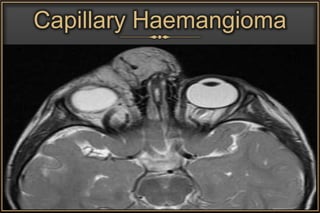

• Extraconal lesions

 Capillary Haemangioma

Capillary Haemangioma